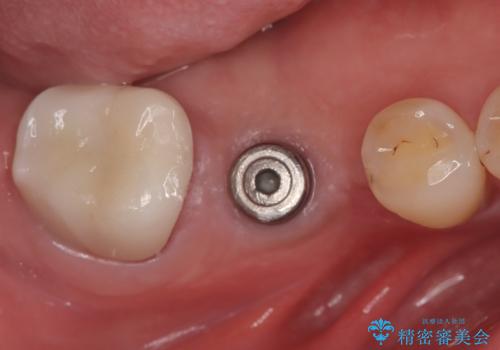

スクリューリテインにて上部構造を連結しています。